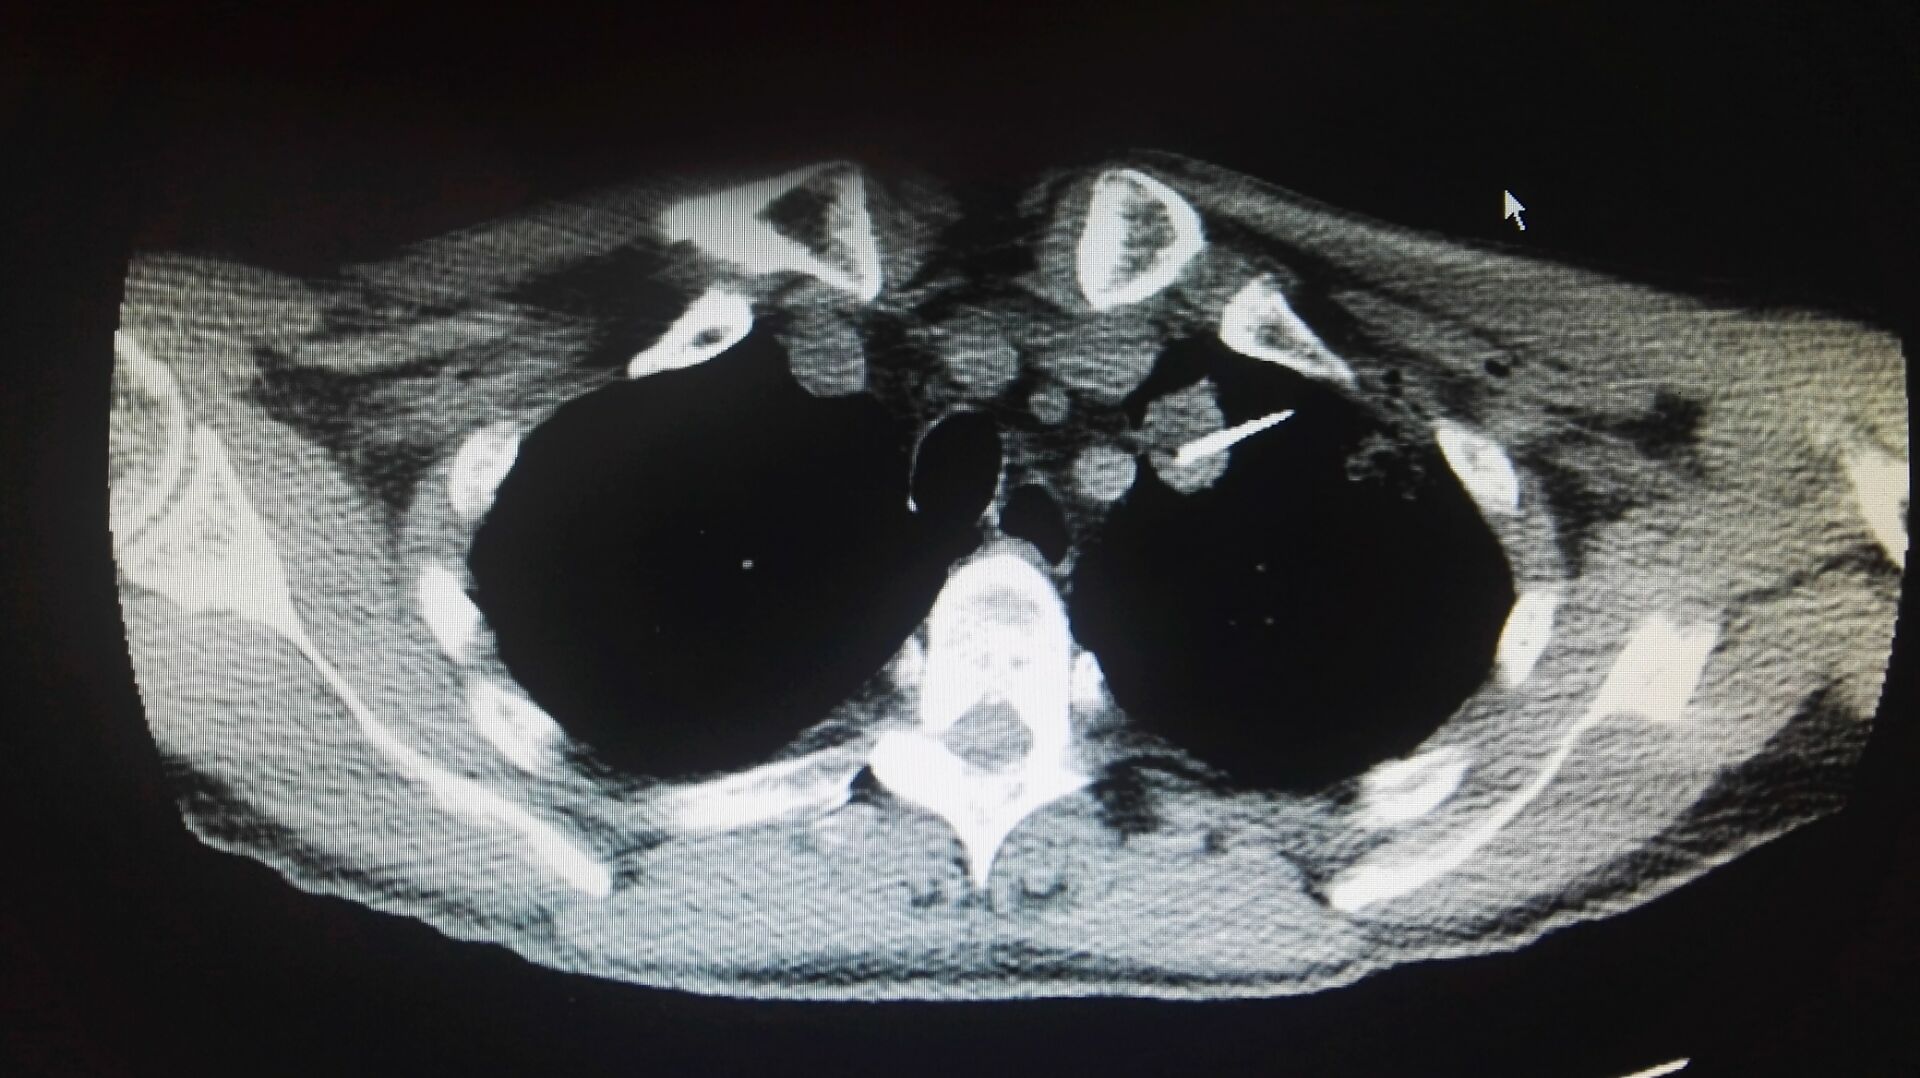

由于患者的肿瘤位置比较特殊,距离左侧颈总动脉仅有3毫米的距离,进行消融时,需要医生精确控制周边的方位,稍有不慎就有可能插入周边的血管,导致上下行神经的损伤,引起术后声音嘶哑、膈肌麻痹和术中心脏骤停等,因而手术难度较大,不能有丝毫差错,不仅考验手术医生的技艺,更加需要麻醉的全力配合。麻醉科主任陈永红说:“术中,因为患者需要保持安静、制动,防止咳嗽、肌肉收缩导致组织撕裂与血管被切割等意外的发生,所以要密切观察患者的生命体征特别是呼吸的变化。”因而,在不插管的情况下,如何良好镇痛也考验着麻醉医生的技术。